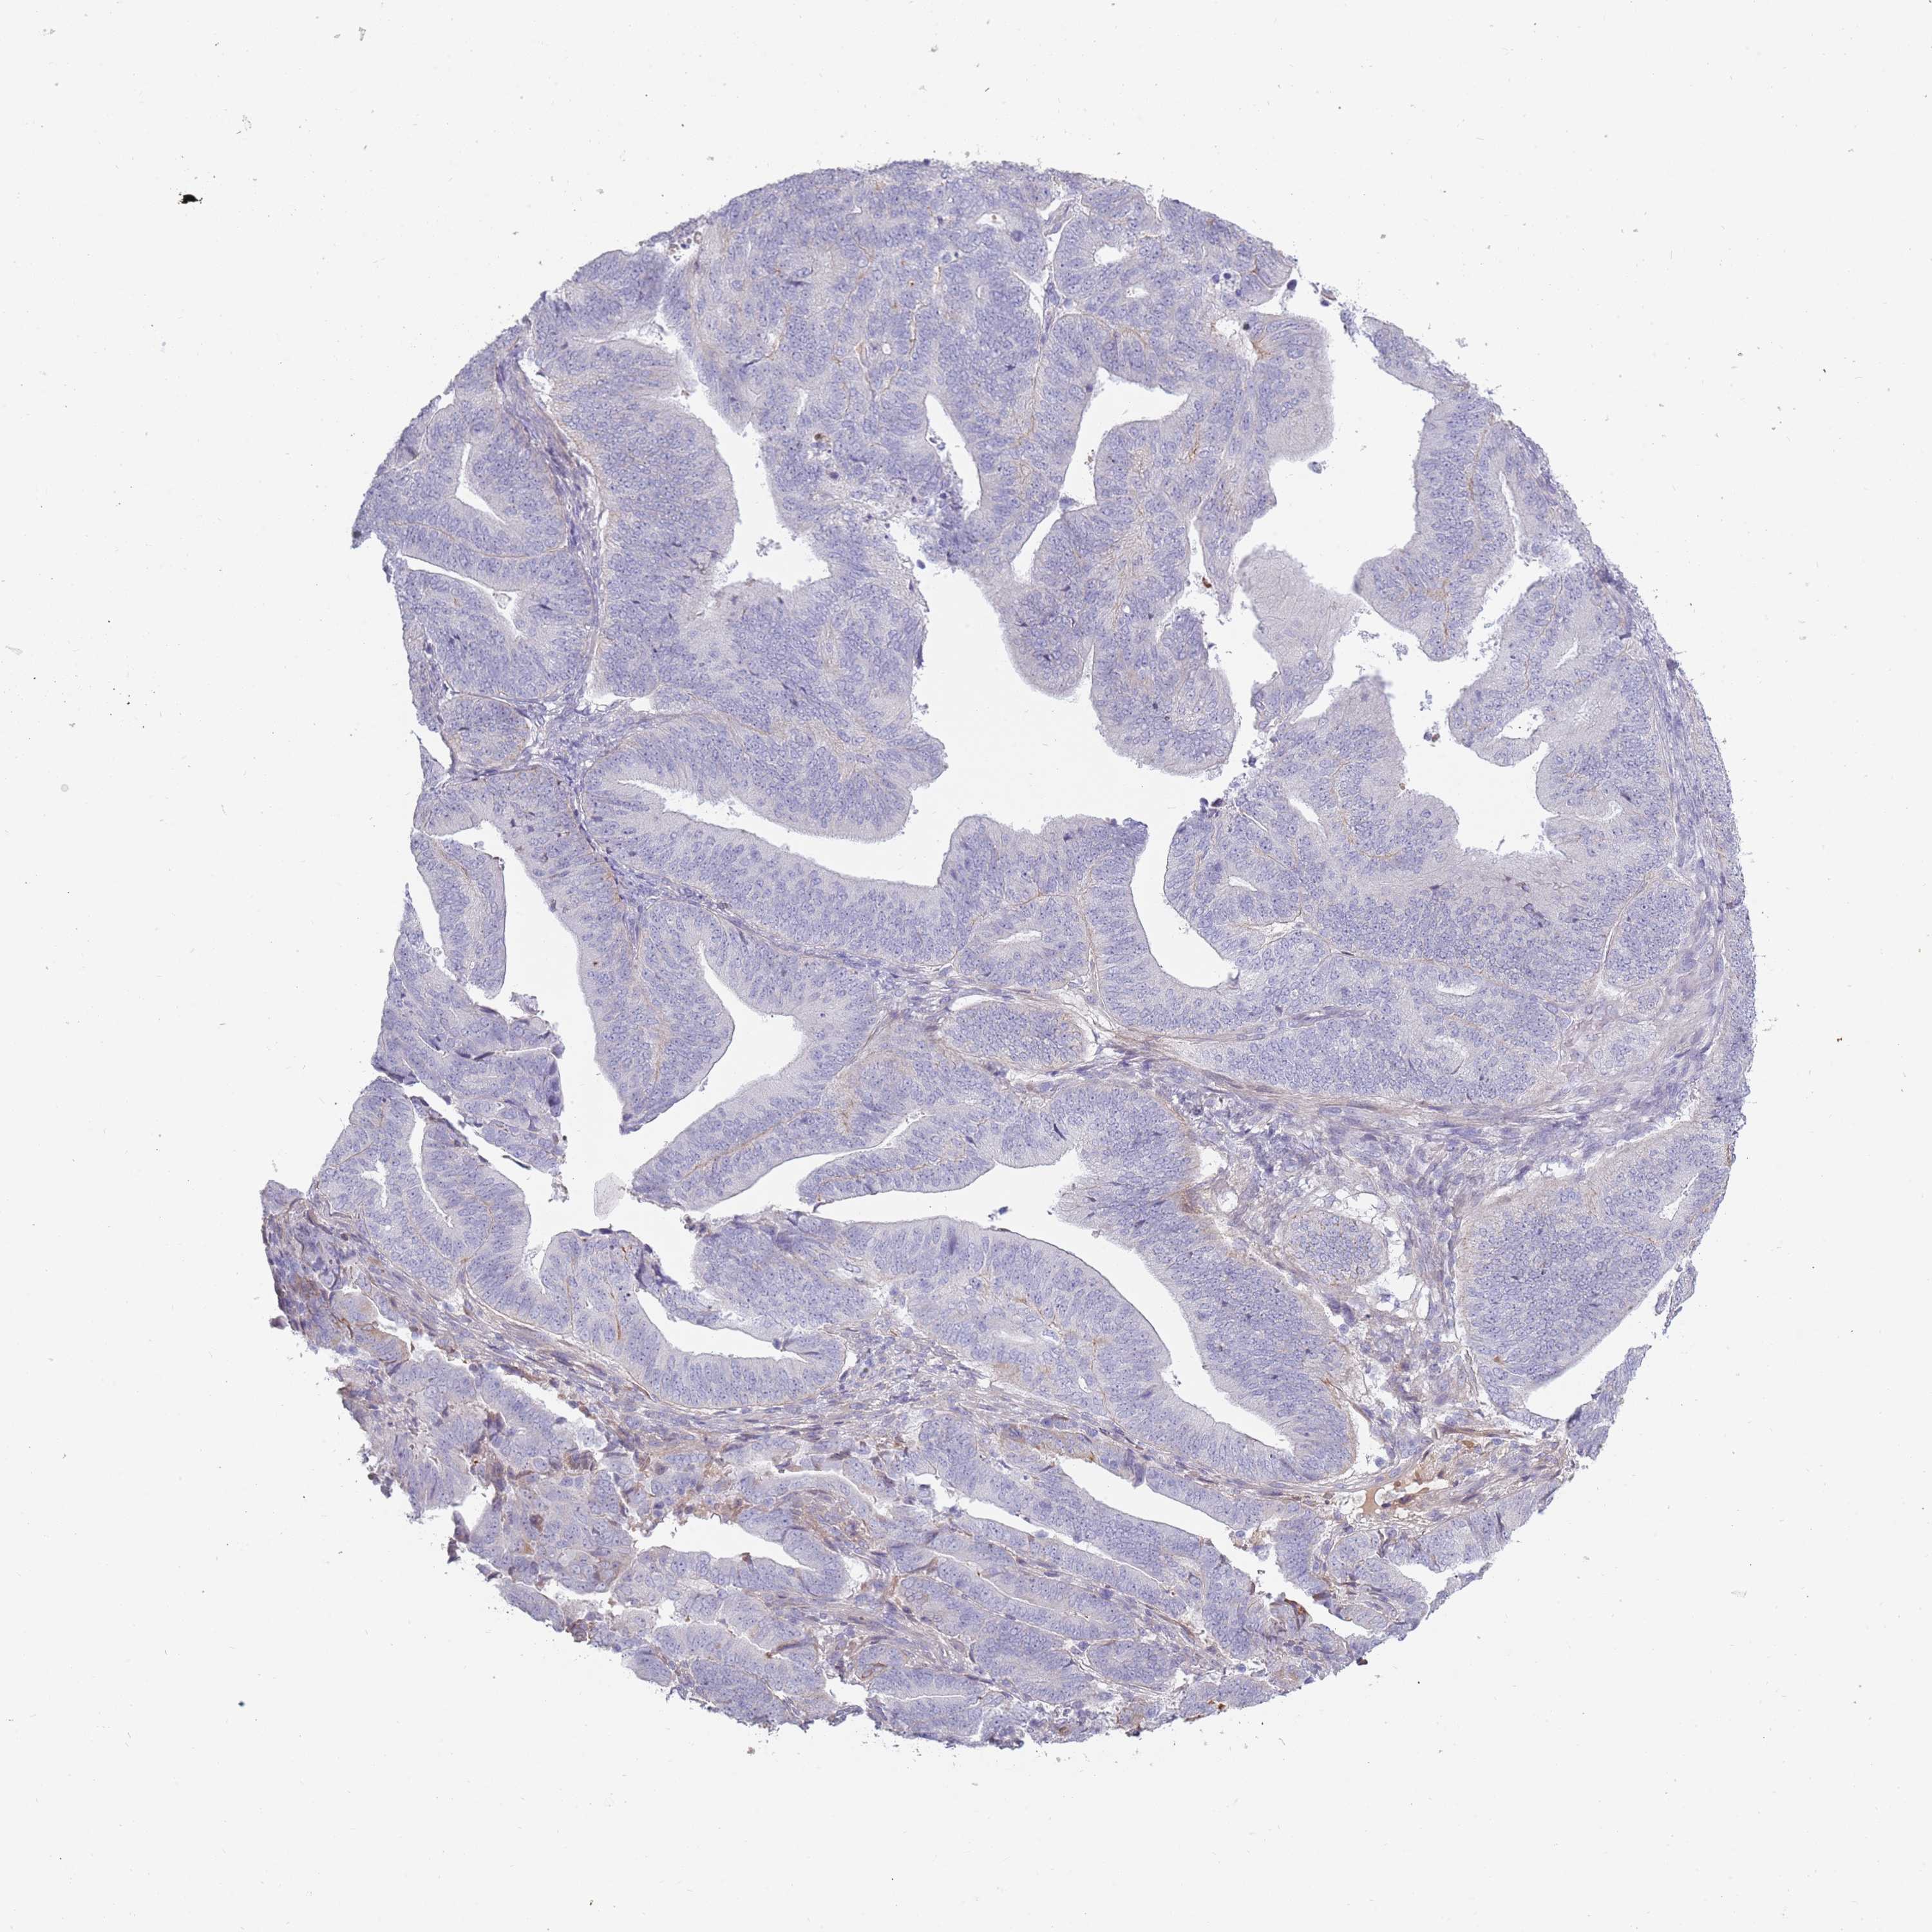

ENDOMETRIAL CANCER - Protein expressioni

A mouse-over function shows sample information and annotation data. Click on an image to view it in a full screen mode. Samples can be filtered based on level of antibody staining by selecting one or several of the following categories: high, medium, low and not detected. The assay and annotation is described here.

Note that samples used for immunohistochemistry by the Human Protein Atlas do not correspond to samples in the TCGA dataset.

Antibody stainingi

Antibody staining in the annotated cell types in the current human tissue is reported as not detected, low, medium, or high, based on conventional immunohistochemistry profiling in selected tissues. This score is based on the combination of the staining intensity and fraction of stained cells.

Each image is clickable and will lead to virtual microscopy that enables deeper exploration of all samples and also displays staining intensity scores, fraction scores and subcellular localization as well as patient and tissue information for each sample.

Antibody HPA047154

Staining

High

Medium

Low

Not detected

Intensity

Strong

Moderate

Weak

Negative

Quantity

>75%

75%-25%

<25%

None

Location

Nuclear

Cytoplasmic/membranous

Cytoplasmic/membranous,nuclear

Adenocarcinoma, NOS